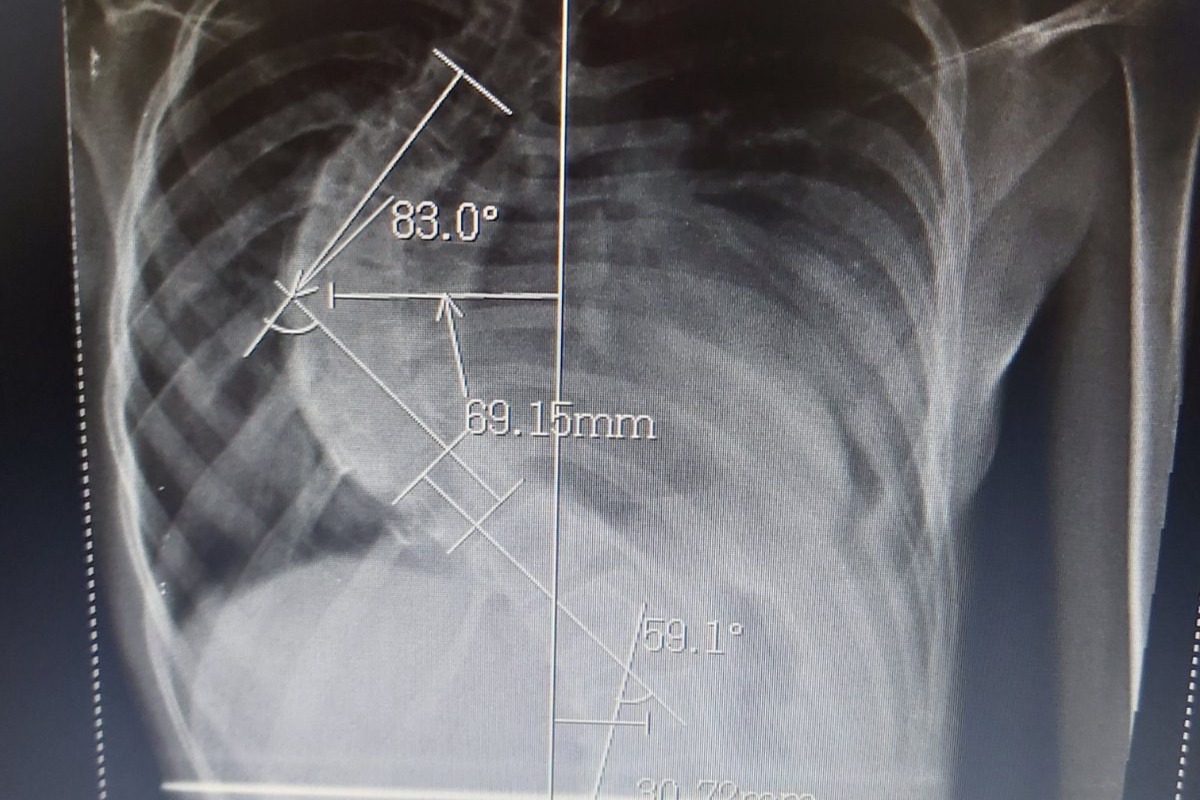

I would like to dedicate this fundraiser to my niece, Sara. Sara was diagnosed with Adolescent Idiopathic Scoliosis when she was 10 years old. She is now 14 and she has gone through so much since then. Over the course of 4 years, Sara has had countless doctor appointments, X-rays, MRI's and hospital trips to monitor the progress of the curves in her spine. During this time she underwent very intense Schroth method camps in Serbia and Bulgaria. She was also in a custom hard-shell back brace for 18 hours a day for more than 2 years in an attempt to straighten her spine as she grew. Her curves were resistant to the brace and the exercises, and unfortunately did not improve as we hoped. Sara’s curve has rapidly worsened this year and she is now dealing with a curve of 83 degrees. A curve of this magnitude causes her lungs to be slowly crushed as the curve worsens. She's dangerously close to severe complications and long-term consequences to her quality of life. It’s imperative that she has an operation as soon as possible so that as she continues to grow the condition will not worsen and she is left with irreversible damage to her body.

I would like to dedicate this fundraiser to my niece, Sara. Sara was diagnosed with Adolescent Idiopathic Scoliosis when she was 10 years old. She is now 14 and she has gone through so much since then. Over the course of 4 years, Sara has had countless doctor appointments, X-rays, MRI's and hospital trips to monitor the progress of the curves in her spine. During this time she underwent very intense Schroth method camps in Serbia and Bulgaria. She was also in a custom hard-shell back brace for 18 hours a day for more than 2 years in an attempt to straighten her spine as she grew. Her curves were resistant to the brace and the exercises, and unfortunately did not improve as we hoped. Sara’s curve has rapidly worsened this year and she is now dealing with a curve of 83 degrees. A curve of this magnitude causes her lungs to be slowly crushed as the curve worsens. She's dangerously close to severe complications and long-term consequences to her quality of life. It’s imperative that she has an operation as soon as possible so that as she continues to grow the condition will not worsen and she is left with irreversible damage to her body.